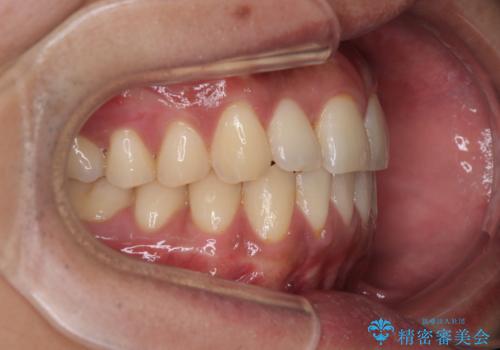

診察したところ、上下顎前歯部に軽度の叢生(ガタつき)が認められます。

目立たない装置を希望されたのでインビザライン ライトパッケージで治療を行うことになりました。